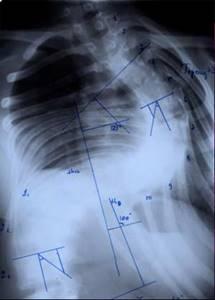

| Больной Т-ов, 16 лет Сколиоз IV степени. До операции |

|

| Больной Сав-ко 15 лет. Кифотическая деформация. До операции |